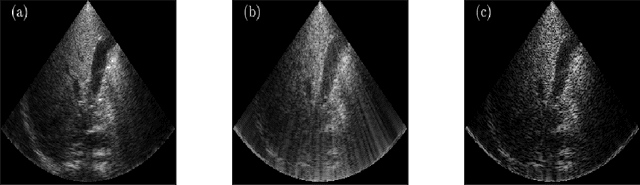

Abstract:The most common technique for generating B-mode ultrasound (US) images is delay and sum (DAS) beamforming, where the signals received at the transducer array are sampled before an appropriate delay is applied. This necessitates sampling rates exceeding the Nyquist rate and the use of a large number of antenna elements to ensure sufficient image quality. Recently we proposed methods to reduce the sampling rate and the array size relying on image recovery using iterative algorithms, based on compressed sensing (CS) and the finite rate of innovation (FRI) frameworks. Iterative algorithms typically require a large number of iterations, making them difficult to use in real-time. Here, we propose a reconstruction method from sub-Nyquist samples in the time and spatial domain, that is based on unfolding the ISTA algorithm, resulting in an efficient and interpretable deep network. The inputs to our network are the subsampled beamformed signals after summation and delay in the frequency domain, requiring only a subset of the US signal to be stored for recovery. Our method allows reducing the number of array elements, sampling rate, and computational time while ensuring high quality imaging performance. Using \emph{in vivo} data we demonstrate that the proposed method yields high-quality images while reducing the data volume traditionally used up to 36 times. In terms of image resolution and contrast, our technique outperforms previously suggested methods as well as DAS and minimum-variance (MV) beamforming, paving the way to real-time applicable recovery methods.